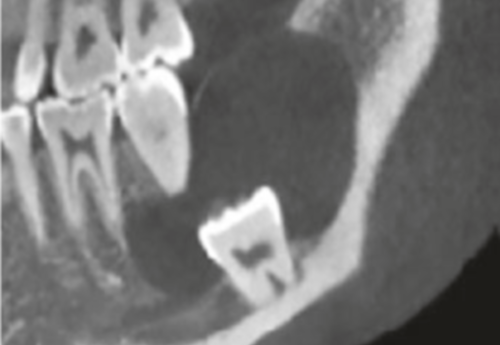

Jei protiniams dantims nėra galimybės tinkamai išdygti, nustatomas dantų susigrūdimas – tokia situacija yra ganėtinai pavojinga, nes susigrūdę dantys gali sukelti infekciją, lemti gretutinių dantų gedimą, dantenų ligas ar cistų formavimąsi. Kai siekiama išvengti šių problemų, odontologai rekomenduoja protinius dantis pašalinti. Prieš tai yra atliekama rentgeno nuotrauka, kuri padeda nustatyti dantų rovimo būtinybę.

Taip yra yra vadinami įstrigę arba nedygstantys protiniai dantys, kurie gali būti visiškai susiformavę, tačiau taip ir neišdygę. Odontologai skiria du pagrindinius protinių dantų retencijos laipsnius:

Esant šiai patologijai odontologai dažniausiai pataria tokius dantis pašalinti, nes priešingu atveju tai gali sukelti tam tikrų komplikacijų, kurių dažniausios yra šios: